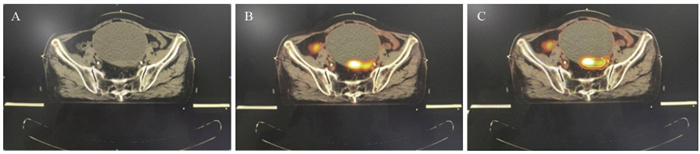

方法 采用18F-FDG PET-CT对38例治疗后复发的腹盆腔肿瘤患者进行模拟定位, 分别根据CT影像及18F-FDG PET-CT拟定全身治疗方案及放疗靶区勾画, 对比二者差异。

结果 在38例患者中, 21.1%(8/38)发现了盆腹腔外远处转移, 改变了治疗方案。34例(89.5%)放射治疗靶区发生了改变。GTVPET-CT的均值为118.14 cm3, GTVCT的均值为148.53 cm3(P=0.044)。

结论 18F-FDG PET-CT模拟定位对于复发盆腹腔肿瘤患者, 完善了肿瘤再分期, 改变了部分患者治疗方案, 更加精确放射治疗靶区。